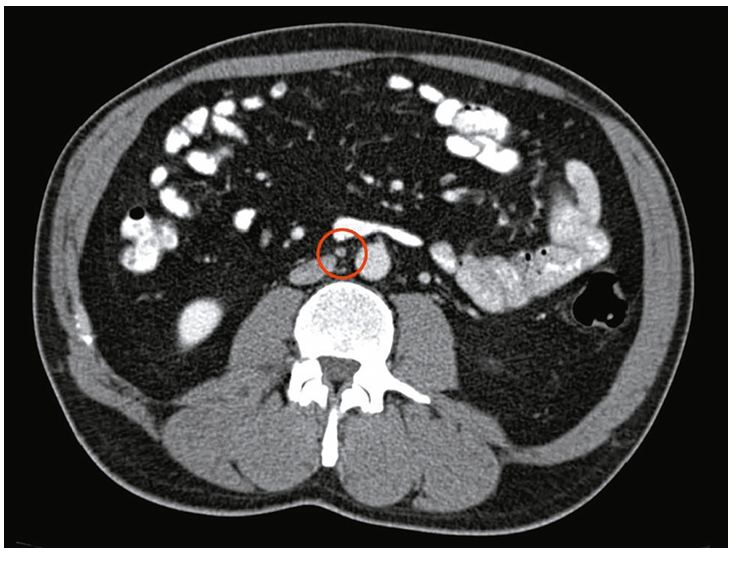

🔹 2. Інструментальні методи

КТ або МРТ органів черевної порожнини та малого таза — для оцінки стану заочеревинних лімфовузлів і поширення процесу.